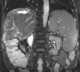

Calcified inferior vena cava thrombus and adrenal hemorrhage